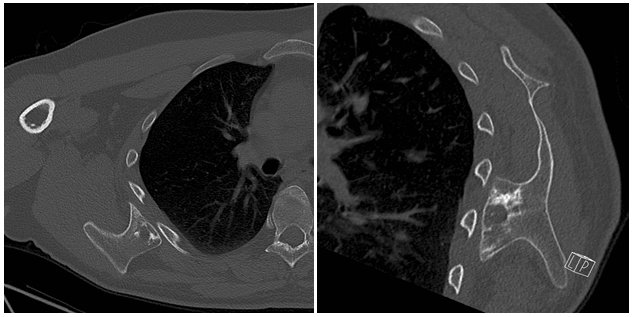

In our outpatient department a 33-year-old male presented with complaints of continuous pain around his right shoulder and scapula. The pain developed gradually over the last 2 years, making it impossible to sleep on his right shoulder and he had complaints of pain during daily labour. When moving his right shoulder, crepitation was noted by the patient around the right scapula. Family history was not contributory and there was no history of trauma. A clinical examination showed an asymmetry of his scapulae with a wing-like prominence of his right scapula (Figure 1). Scapulothoracic crepitus was noted when abducting his right shoulder. A full range of motion was found in both shoulders. Radiographic evaluation showed an irregular bony structure extruding from the scapula (Figure 2). Computed tomography (CT) revealed an osteochondroma along the medial border on the ventral surface of the right scapula (Figure 3). In addition a magnetic resonance imaging (MRI) was performed, showing a bone lesion originating from the anterior side of the scapula with slight bursa formation, most likely to be an osteochondroma (Figure 4). There were no signs of malignant transformation. Since the lesion prevented the patient from performing his job and the complaints of his shoulder worsened over time, surgical resection was proposed.

Figure 3 CT-scan of the right shoulder showing a osteochondroma of the scapula arising from the anterior surface of the scapula.